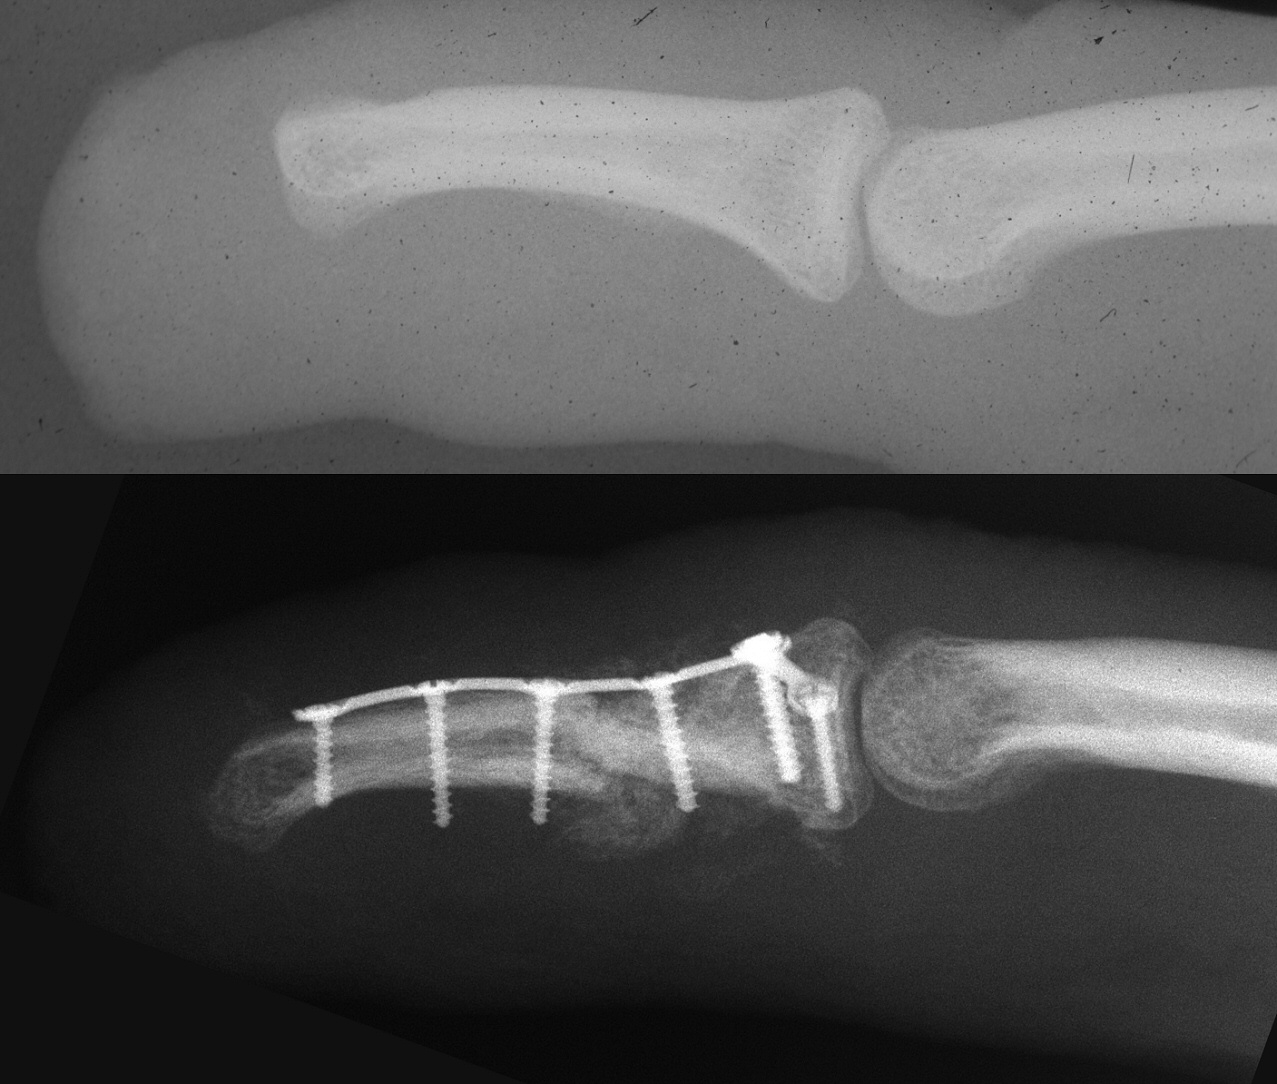

Clinical Examples: Finger distraction lengthening with palatal expansion clamp and intercalated bone graft

These are two cases of traumatically shortened fingers lengthened with paired palatal expansion clamps used to construct miniature progressive skeletal distraction followed by intercalary bone grafting

Case 1. This patient had an unstable small fingertip following a saw injury which resulted in loss of the central half of the distal phalanx of the small finger.

Case 2. Middle phalanx lengthening with proximal metaphyseal osteotomy, distraction and bone graft: